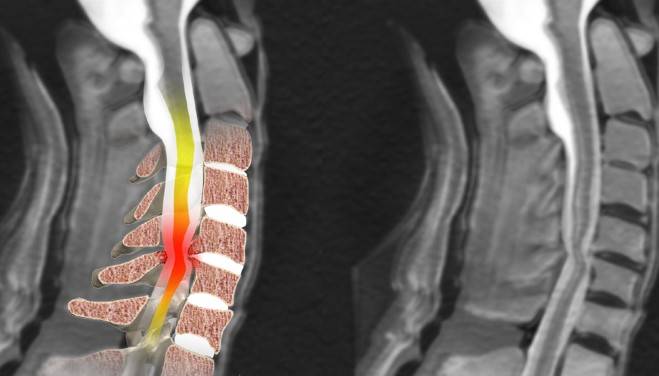

Во время волнового облучения организма, происходит дифференциальная реакция, с последующей ее визуализацией. Здоровые ткани организма излучают волны, отличные от тех, которые отражают ткани, подвергшиеся патологическому изменению. Разная длина волн позволяет сформировать цифровую 3D картинку, где четко видно локализацию и характер патологии. Вот что может показать расшифровка МРТ-снимков после обследования шейного отдела позвоночника:

- Различные деформации шейных позвонков. При заболеваниях, сопровождающихся дегенеративными изменениями костной и хрящевой тканей, на позвонках наблюдаются наросты и структурные изменения (пористость, уплотнение).

- Межпозвоночная грыжа. В результате смещения позвонков, происходит разрыв фиброзного кольца и смещение межпозвонкового диска.

- Миеломаляция. В процессе сдавления спинного мозга или при недостаточном его кровоснабжении, МРТ показывает очаги некротизированного спинномозгового вещества.

- Опухоли и метастазы. Контрастное вещество позволяет выявить любые новообразования, даже на начальной стадии.

- Сдавление нервных корешков и деформация сосудов.

- Травматические деформации мягких и костно-хрящевых тканей.

- Врожденные дефекты.

Любое дегенеративное изменение, локализованное в области шеи, отчетливо видно на снимках, сделанных в нескольких проекциях. Это позволяет установить не только наличие и расположение патологии, но также степень ее тяжести, характер и источник возникновения деструктивного процесса в позвонках, дисках, сосудах, нервных окончаниях и костно-мышечных тканях.